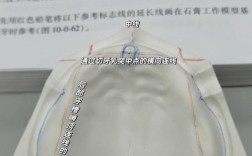

- 取模: 使用硅橡胶或聚醚等高精度印模材料取模,灌制石膏模型。